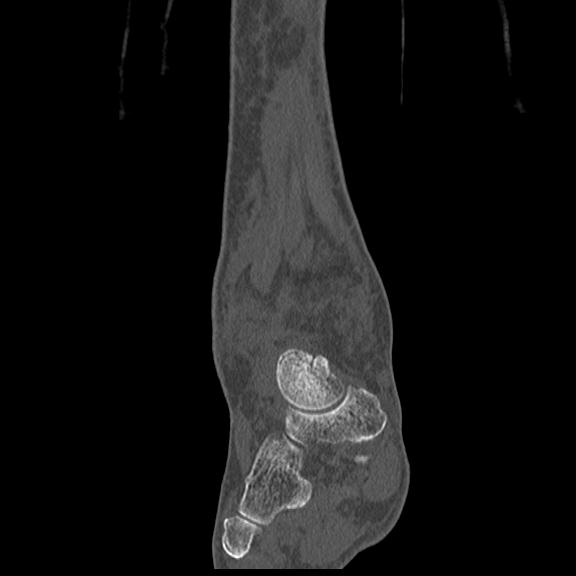

102755 1/4 2R 1/15 2R 右足関節 68歳女性 右三果脱臼骨折